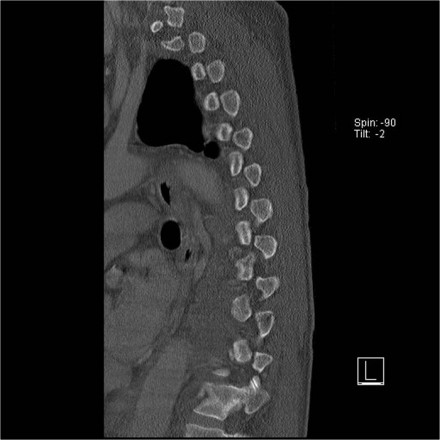

Case 3

Look at the images.

How would you describe the morphology and the PLC?

The findings are:

- Morphology: Translation - 3 points

- PLC: always disrupted in translation - 3 points

- TLICS: 6 points